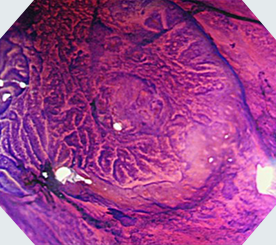

NBI

NBI+拡大観察

クリスタルバイオレット+拡大観察ハイビジョン対応の高画質で、拡大観察できる光学ズーム機能を搭載。NBIとの併用により、腫瘍などの詳細な観察・診断が可能です。